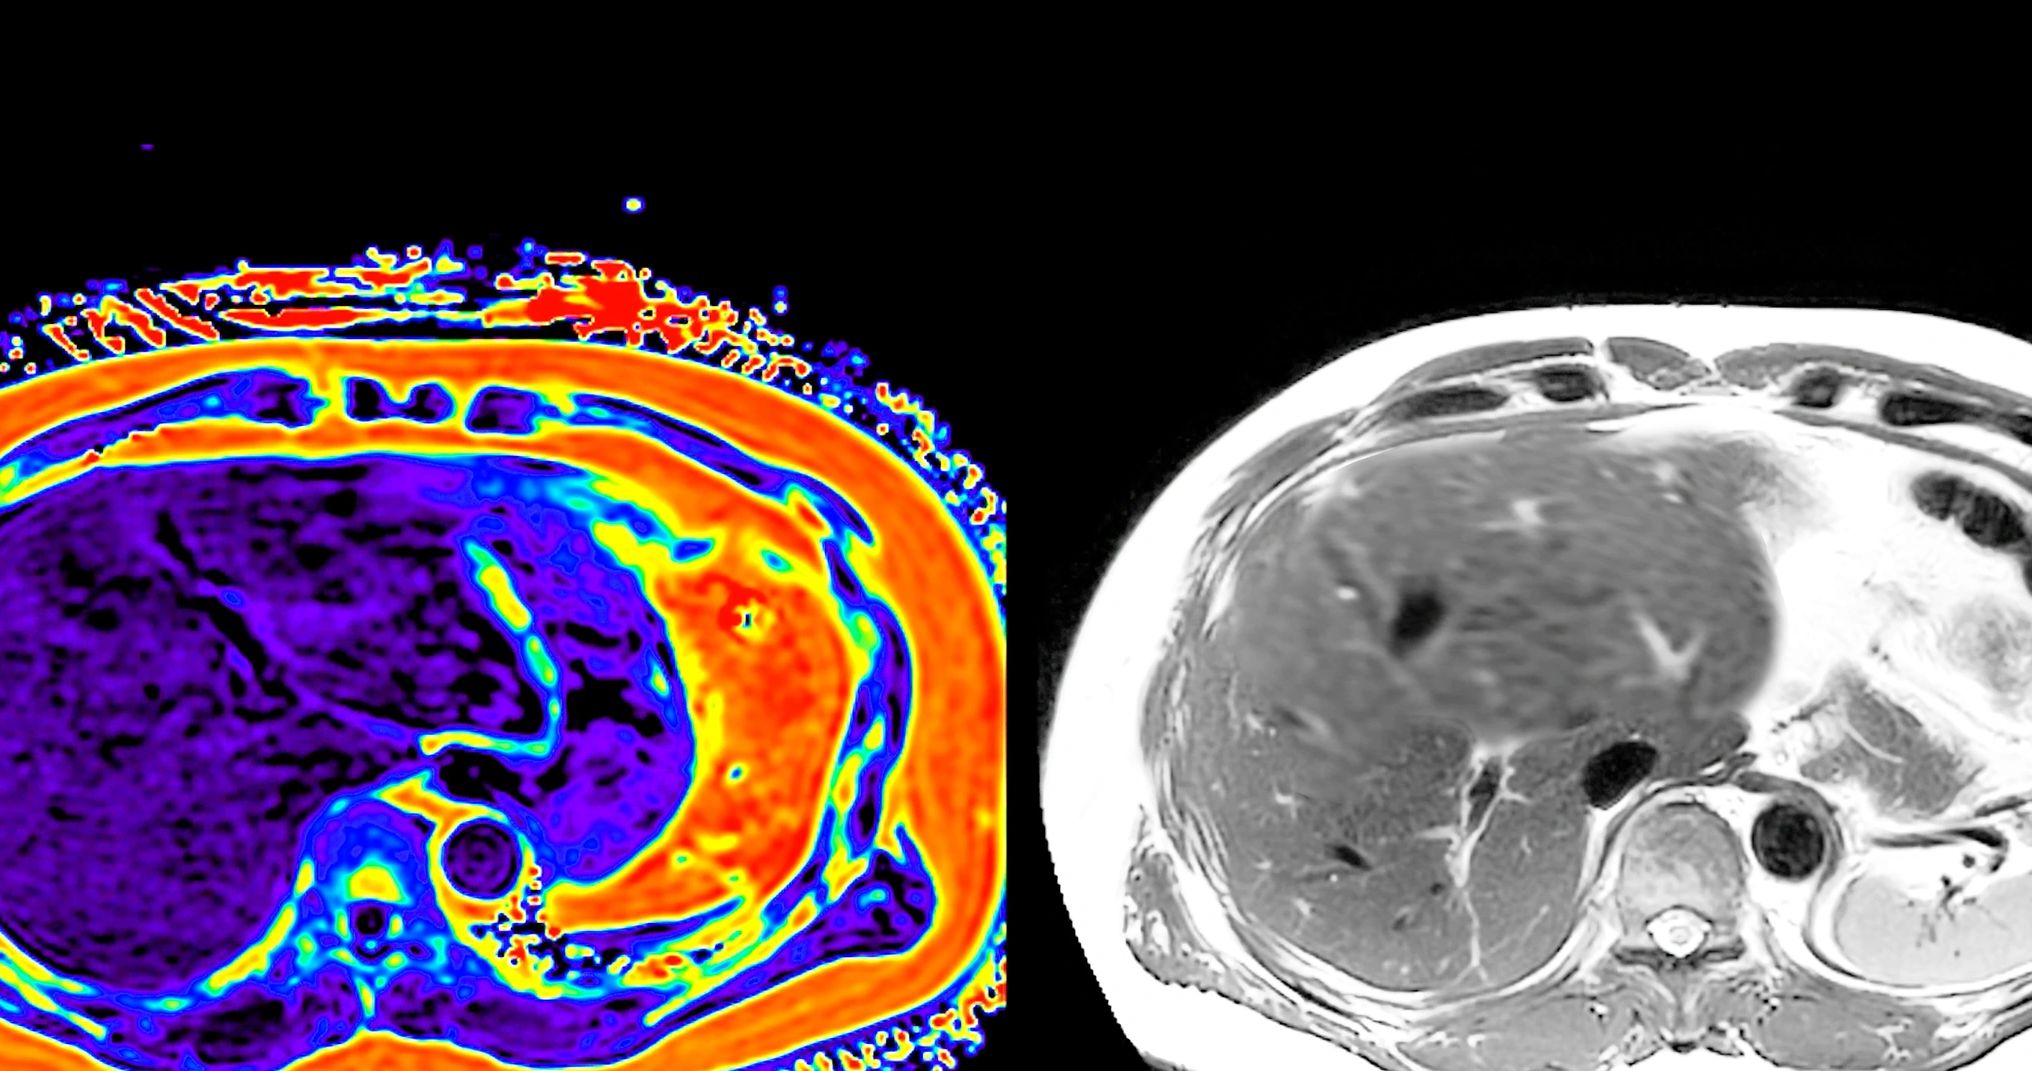

Karaciğer Kitlesi

Tanı araçlarının çeşitlenip gelişmesi ve sağlık hizmetine ulaşımın yaygınlaşması ile giderek artan sıklıkla karaciğer kitleleri ile karşılaşılmaktadır. Bu kitleler iyi huylu veya kötü huylu olabilir. Bu kitlelerin dikkatli olarak değerlendirilmesi gerekir.

Herhangi bir sebeple karaciğer görüntülemesi uygulanan 100 kişiden yaklaşık 6'sında karaciğerde kitle saptanmaktadır. Bu saptanan kitlelerin ne kadarının iyi huylu olduğu konusunda net bir istatistik bulunmamakla birlikte daha büyük bir çoğunluğunun iyi huylu olduğu tahmin edilmektedir. Ancak iyi huylu olanlarının dahi bir kısmında ameliyat gerekliliği doğabileceğinden her karaciğer kitlesinin, karaciğer hastalıklarının cerrahisi konusunda uzmanlaşmış bir cerrah tarafından kişi özelinde değerlendirmesi gerekir.

Teşhisi,  risk taşıyan hastalarda karaciğer dinamik kontrastlı BT veya MRG ile konulabilir.